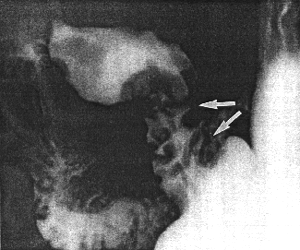

Case 28.5 J.M., 45 year old male. The pyloric sphincteric cylinder remained partially contracted throughout the radiographic examination, with complete absence of normal, cyclical contraction and relaxation. At least one prominent, circumferential mucosal fold, which did not change in position, was present in the partially contracted cylinder (Fig. 28.5). Initially it was difficult to distinguish between a permanent, circumferential mucosal fold and a prepyloric septum. Endoscopy revealed prominent, thickened prepyloric mucosal folds with an abnormal, whitish, granular surface. Endoscopic biopsy showed lymphocytic and plasma cell infiltration of the lamina propria; in some areas atypical epithelium, presumably due to inflmmatory change, was seen. The endoscopic diagnosis was chronic "antral" gastritis.

![]() |

| Fig. 28.5. Case J.M. Partial contraction of sphincteric cylinder, with absent cyclical activity. Prominent static, circular mucosal fold in cylinder (arrow) |

According to Nesland and Berstad (l985) and Karvonen et al. (l987), erosive prepyloric change (EPC) was a condition characterized by standing mucosal folds and erosions; it was diagnosed endoscopically and appeared to be an entity of its own. Radiographically a standing mucosal fold may also be recognized, as seen in Fig. 28.5. In this case it concerned a circular fold which failed to change in position. It was associated with lymphocytic and plasma cell infiltration, no mention being made of erosions.